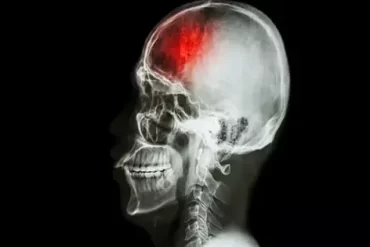

Stroke is amongst the most unpleasant and life-threatening neurological disorders. This doesn’t...